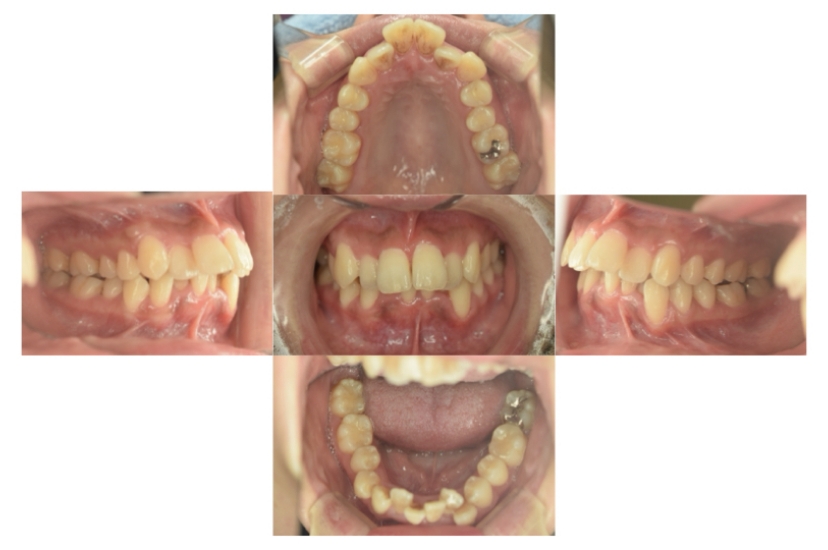

症例9

叢生

抜歯

ブラケット矯正

症例解説

上下顎叢生(上下の前歯のガタガタ)のケースです。

装置はラビアル(上下表側)で、右上以外の小臼歯を3本、右上は犬歯の抜歯を行っています。抜歯したスペースを使って、上下の前歯の後方移動と叢生(ガタガタ)の改善を行っています。

主訴 八重歯を治したい。

年齢・性別 27歳 女性

お住まいの地域 東京都港区

治療方針 抜歯スペースを利用して上下前歯の叢生(ガタガタ)の改善

抜歯部位 上顎右側犬歯、上顎左側第一小臼歯、下顎両側第一小臼歯

使用装置 ラビアル(上下表側)、顎間ゴム

治療期間 3年3か月

治療回数 25回

リテーナー クリアリテーナー

BEFORE